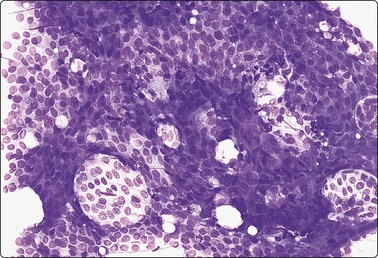

image image image

Fig. 7.8 Lactating breast

Dispersed acinar cells with abundant pale and fragile cytoplasm, rounded nuclei and prominent central nucleoli; background of lipid secretions (A, MGG, HP; B, H & E, HP oil); (C) Corresponding tissue section (H&E, IP).

Criteria for diagnosis

Cellular smears,

Poorly cohesive, mainly dispersed epithelial cells of acinar type,

Cells have abundant fragile cytoplasm with secretory vacuoles and frayed borders,

Rounded vesicular nuclei and central nucleoli,

Dirty background due to lipid secretion and stripped nuclei with prominent nucleoli,

Single bipolar nuclei difficult to find.

FNB is very useful in reducing surgical intervention to a minimum during pregnancy and lactation. The pattern seen in FNB smears of ‘lumps’ in a pregnant or lactating breast can be problematic to inexperienced eyes and cause concern for malignancy.93,94 Smears are usually cellular. The cells are enlarged and arranged in loose groups or singly. The cells have an abundant fragile cytoplasm, vacuolated and finely granular. Nuclei are round, central, larger than the usual ductular cells, and have distinct small nucleoli (Fig. 7.8B). Some epithelial nuclei are stripped of cytoplasm. Single naked bipolar/oval nuclei are difficult to find. The background of abundant milky secretion with numerous lipid droplets seen as vacuoles is characteristic of actively secreting breast tissue and is the main clue to the diagnosis (Fig. 7.8A).